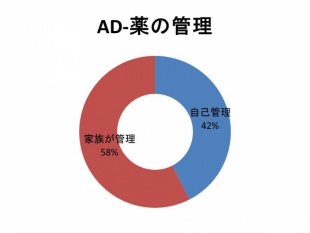

Q 認知症のある人の薬の管理は?

認知症のある方は、薬を管理ができない場合が多くあります。薬を飲み忘れてしまうことが多いですので周囲のサポートが必要です。認知症の薬が進行予防の効果があることはわかっていますので、忘れずに飲んでもらうことが大切です。

当院での調査でも自分で薬が管理できている人は半分以下でした。